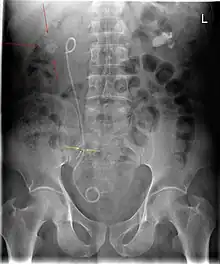

Abdominal X-ray showing a double J stent to relieve colics from kidney stones (red arrows). The stone obstructing the ureter is also visible (yellow arrows).